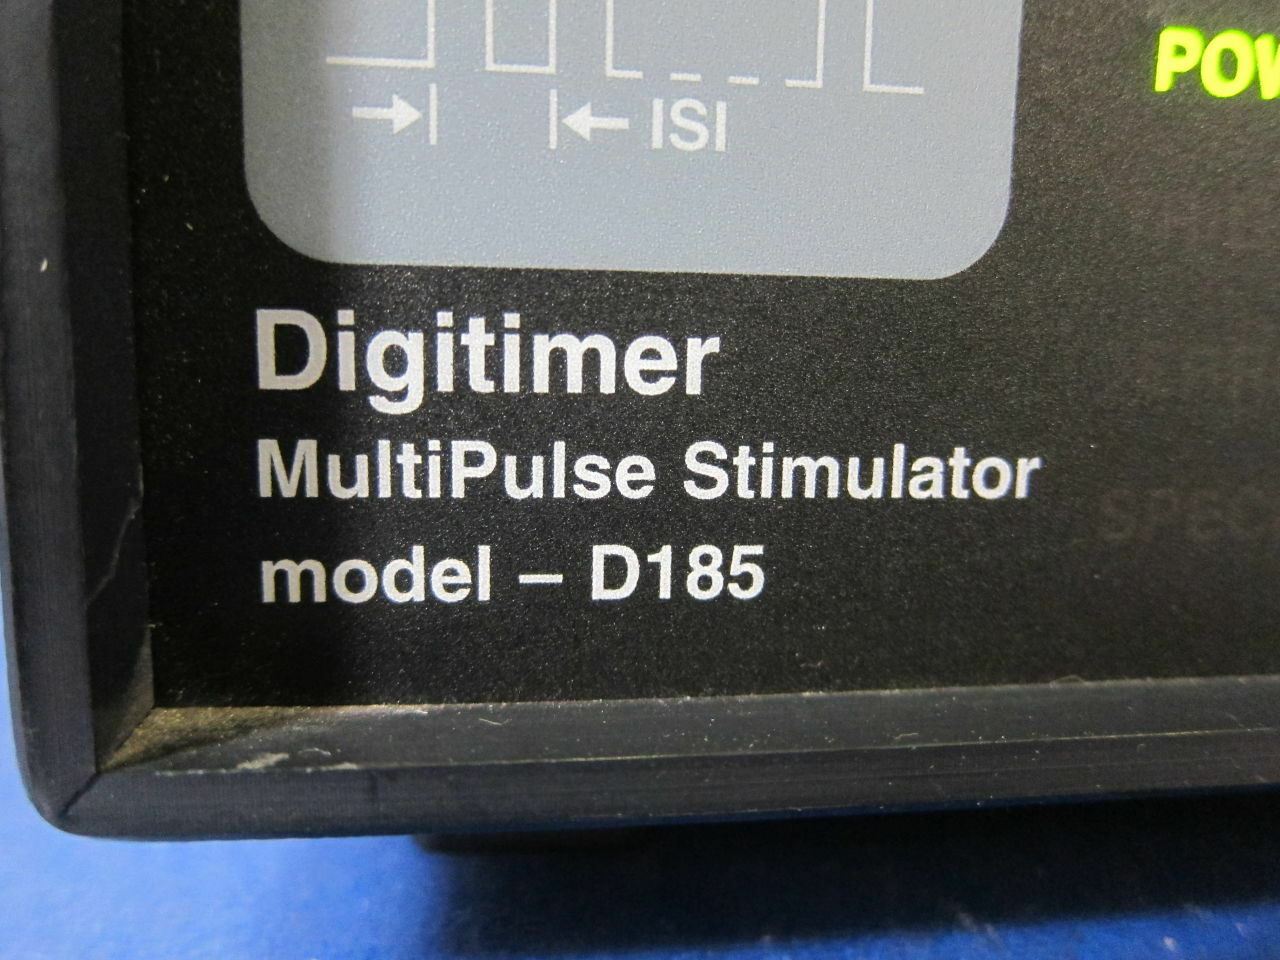

Save $ 89.82

DIAGNOSTIC ULTRASOUND MACHINES FOR SALE

Digitimer D185 MultiPulse Transcranial Cortical Stimulator (595DM)

Sale price$ 409.18

Regular price$ 499.00